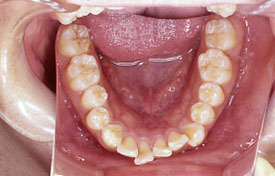

インビザラインの治療例:CASE-2

| プロフィール | 15歳 男性 |

| 所見 | アメリカから転院されて来られた方です。 インビザラインで上下顎の矯正治療を開始し下顎はアメリカで終了しており、上顎のみ治療の後期を担当しました。 アイライナーの装着は、1日平均22時間ほどでした。 |